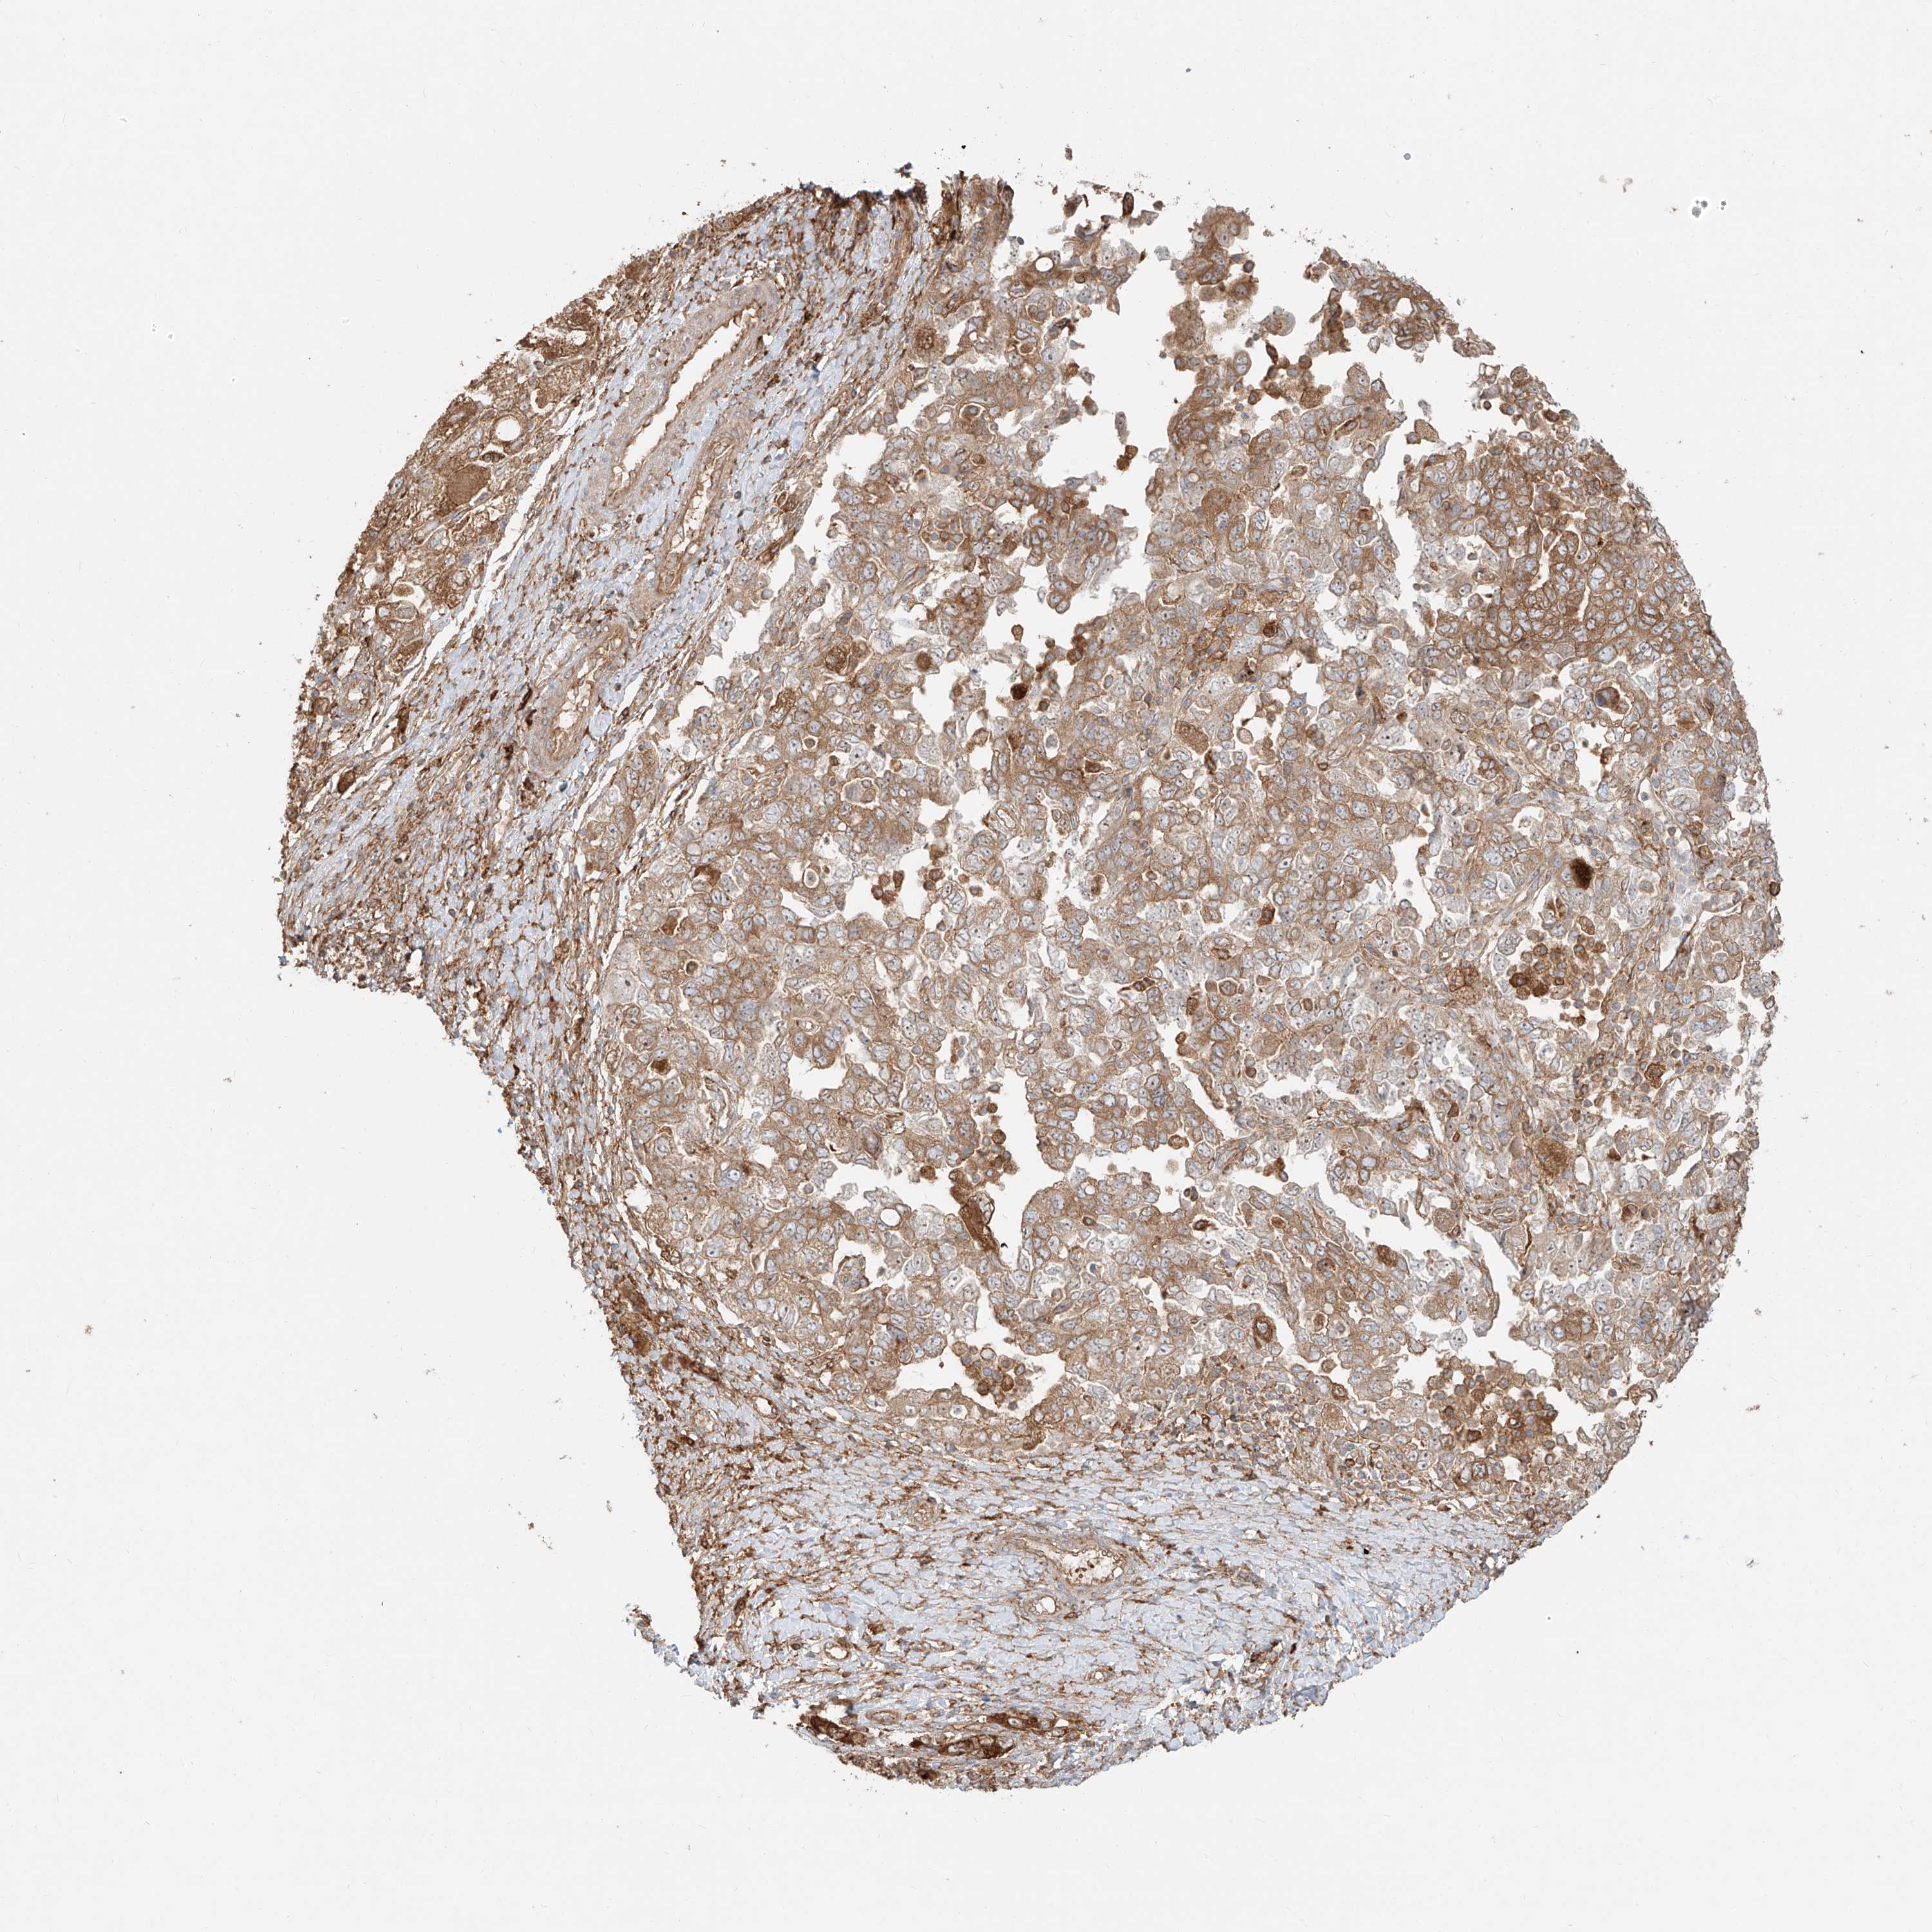

OVARIAN CANCER - Protein expressioni

A mouse-over function shows sample information and annotation data. Click on an image to view it in a full screen mode. Samples can be filtered based on level of antibody staining by selecting one or several of the following categories: high, medium, low and not detected. The assay and annotation is described here.

Note that samples used for immunohistochemistry by the Human Protein Atlas do not correspond to samples in the TCGA dataset.

Antibody stainingi

Antibody staining in the annotated cell types in the current human tissue is reported as not detected, low, medium, or high, based on conventional immunohistochemistry profiling in selected tissues. This score is based on the combination of the staining intensity and fraction of stained cells.

Each image is clickable and will lead to virtual microscopy that enables deeper exploration of all samples and also displays staining intensity scores, fraction scores and subcellular localization as well as patient and tissue information for each sample.

Antibody HPA031410

Staining

High

Medium

Low

Not detected

Intensity

Strong

Moderate

Weak

Negative

Quantity

>75%

75%-25%

<25%

None

Location

Nuclear

Cytoplasmic/membranous

Cytoplasmic/membranous,nuclear

Cystadenocarcinoma, serous, NOS

Carcinoma, endometroid

Cystadenocarcinoma, mucinous, NOS

Carcinoma, NOS